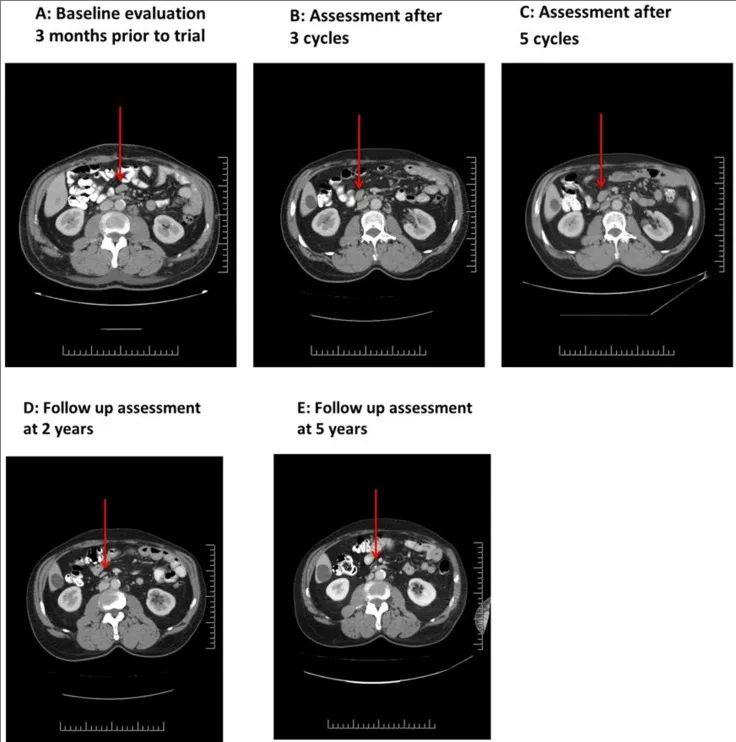

值得一提的是,其中一位60岁患霍奇金淋巴瘤(结节硬化亚型)的男性患者(患者03),治疗后存活长达10 年!既往曾接受过GDP 挽救性化疗(吉西他滨、地塞米松、顺铂)、自体造血细胞移植(AHCT)、沙利度胺+长春花碱、吉西他滨单药治疗等,但病情仍进展,并出现腋窝和腹股沟淋巴结肿大,治疗前CT扫描显示,双侧腋窝淋巴结肿大,最大的淋巴结长轴为 2.5 cm,此外还有小的肠系膜和主动脉旁淋巴结(1 cm)(详见图2A)。此时临床已经没有适合他的其他疗法了,遂入组接受了5个周期的NK-92治疗。

结果显示:在第一周期第23天的中期评估中,病情稳定,最大的腋窝淋巴结略有缩小。3个周期结束时的影像学显示,该患者的一些淋巴结缩小(详见图2B)。虽然在5 个周期结束时,影像学显示淋巴结略有肿大(详见图2C);但在接下来的24个月内,所有疾病部位均得到缓解(详见图2D、图2E)。大约1年后,该患者因皮肤带状疱疹感染的急性播散性脱髓鞘性脑脊髓炎,而接受类固醇治疗。在接受类固醇治疗并在 6 个月内缓慢减量后,他的神经系统完全康复。在停止任何抗癌治疗后,他一直处于临床和放射学缓解状态,在参加本次试验10年后的最近一次随访中,他无症状且未检测到疾病。

▼03号患者NK-92细胞治疗前后的连续CT扫描对比

▲图源“Oncotarget”,版权归原作者所有,如无意中侵犯了知识产权,请联系我们删除

注:

①图A:NK-92治疗前的CT图像;

②图B:NK-92治疗3个周期的CT图像;

③图C:NK-92治疗5个周期的CT图像;

④图D:NK-92治疗2年后的CT图像;

⑤图E:NK-92治疗5年的长期随访中,肠系膜淋巴结外观。